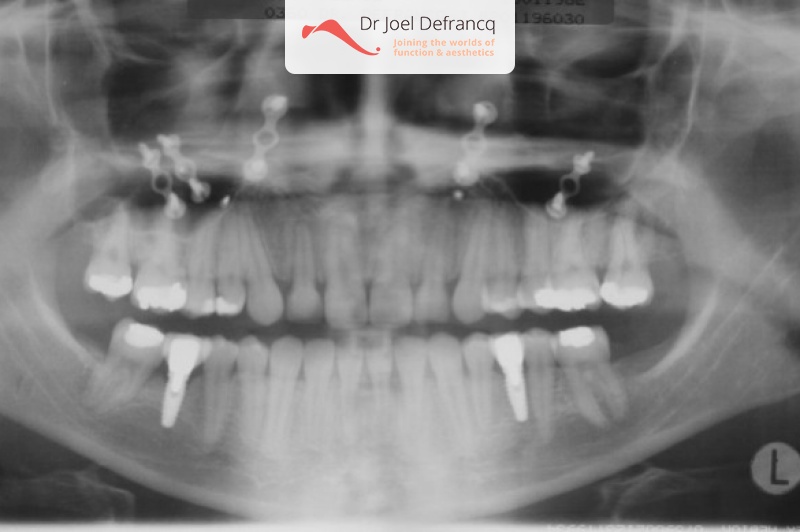

Diagnose van het gezicht

- Te korte bovenkaak

Kaakchirurgie

- Vertikale verlenging bovenkaak (Le Fort I)